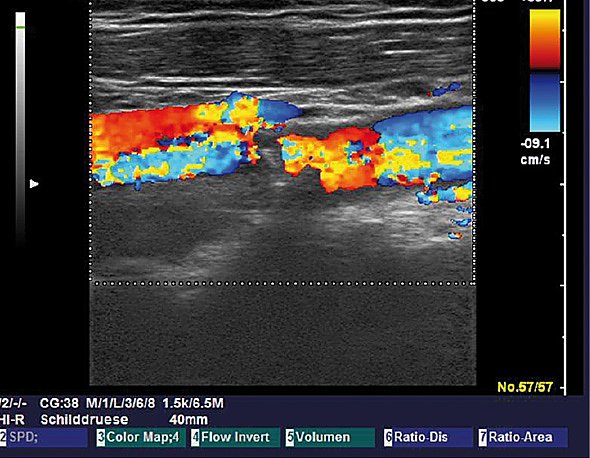

Der Ultraschall ist aus der modernen Radiologie nicht wegzudenken. Ohne Nebenwirkungen können so wichtige Informationen über Lymphnoten, Speicheldrüsen, Oberbauchorgane aber auch Gelenke, Sehnen und die Brustdrüse gewonnen werden. je nach Tiefe des zu untersuchenden Organs werden hierfür verschiedene Schallköpfe verwendet. Je höhe die Frequenz der Wellen hierbei ist, um so bessere und genauere Aussagen und Bilder kann man erhalten, allerdings ist die Eindringtiefe in den Körper für die Schallwellen geringer, je höher Frequent der Schallkopf ist. Deshalb braucht man im Alltag sowohl der Sectorschallkopf als auch einen möglichst hoch auflösenden Schallkopf. Wir haben mit einem linearen Schallkopf bis 14MHz, einem weiteren linearen bis 13 MHz und einem Sektorschallkopf bis 10MHz alle technischen Voraussetzungen für einen hochqualifizierten Ultraschall in der Radiologie, der ebenfalls ambulant und stationär angeboten wird. Besonderheit hierbei ist, dass durch die Elastographiesoftware die Härte eines tumorverdächtigen Befundes ermittelt werden kann, was häufig hilfreich ist, um zu entscheiden, ob es sich um einen gut- oder bösartigen Tumor handelt. Hierüber wurden verschiedene Arbeiten durch Prof. Malich publiziert. Als Alleinstellungsmerkmal ist der Ultraschall von Lymphknoten, Speicheldrüsen und dem Hoden als Kassenleistung an der Radiologie des Südharzklinikums abrechenbar neben den sonst üblichen sonografischen Untersuchungen. Auch über die Lymphknotensonografie wurden mehrere Publikationen veröffentlicht. Darüber hinaus kann man über die Nutzung des sogenannten Dopplereffekts die Durchblutung von Tumoren, Drüsen, Lymphknoten und Gefäßen beurteilt werden.